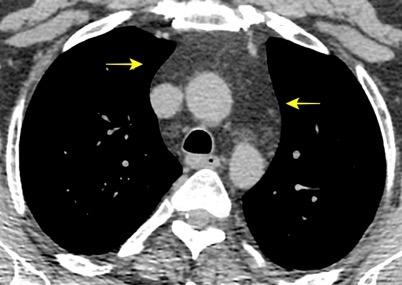

Triada de Garland

Ganglios paratraqueales derechos e hiliares bilaterales

95% de pacientes tienen ganglios hiliares bilaterales aislados o con afectación mediastínica (espec. paratraqueal derecho).

Criado E et al. Pulmonary sarcoidosis: typical and atypical manifestations at high-resolution CT with pathologic correlation. Radiographics. 2010